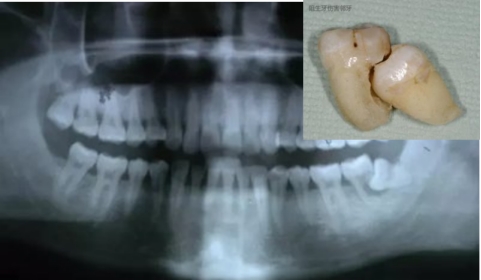

阻生牙(impacted teeth)是指部分萌出或完全不能萌出,且以后也不会自行萌出的牙。好发部位为下颌第三磨牙、上颌第三磨牙及上颌尖牙,其中阻生第三磨牙也叫做阻生智齿。

(2)经急性期治疗待炎症消退后,需尽早拔除阻生牙。